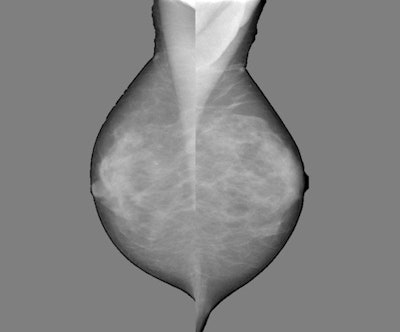

Software by New Zealand-based Volpara "provides tissue volume and dense tissue volume for each pixel location," she said. "The most recent version also provided us with a density map. For each pixel, we know the amount of glandular tissue in volume and centimeters."

Breast density mapping software is enabling more nuanced calculations of breast density measurements in terms of predicting which breast density patterns are more likely to be associated with interval cancers. The Nijmegen researchers hope to use this information to optimize the selection of women for supplemental screening with MRI or ultrasound.